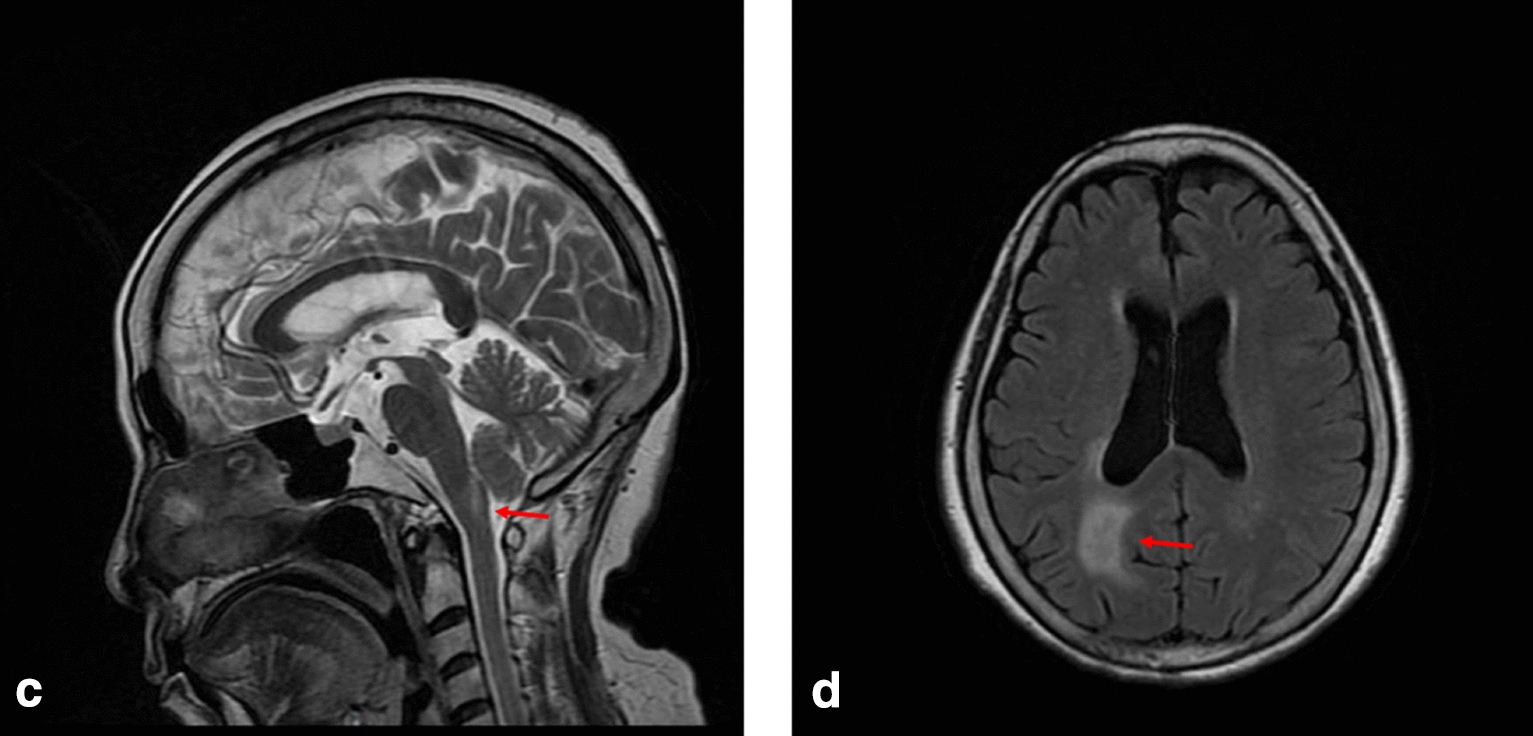

Fig. 2.

MRI T2 sequence of case 2 showing hyperintense in medulla oblongata (highlighted by arrows) in the c sagittal planes, and hyperintense in the right paraventricular and left occipital lobe in the d transverse planes